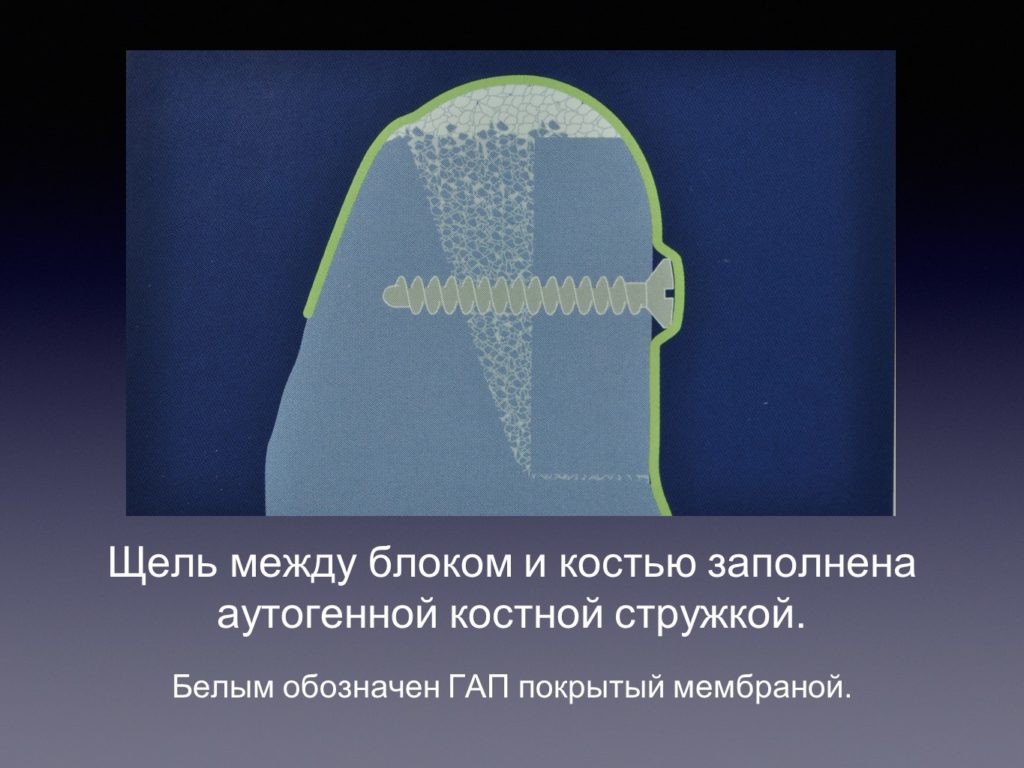

Принцип направленной костной регенерации. Костная регенерация под защитой мембраны Биоматрикс

Принцип направленной костной регенерации. Костная регенерация под защитой мембраны Биоматрикс

Принцип направленной костной регенерации. Костная регенерация под защитой мембраны Биоматрикс